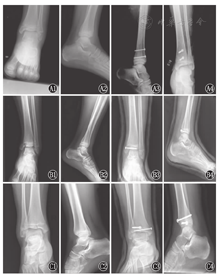

术后复查X线片或CT确定骺板和关节面达到解剖复位,短腿石膏固定4~6周。在石膏固定期间禁止患肢负重。4~6周摄片及临床检查均证实骨折坚强愈合后再让患儿开始进行功能锻炼(图1、图2)。

注:A:Salter-Harris Ⅱ型骨折(男,11岁);B:Salter-Harris Ⅲ型骨折(男,10岁);C:Triplane骨折(男,13岁);1~2:术前;3~4:术后6周

A:Ⅱ type Salter-Harris fracture (male,11 years old);B:Ⅲ type Salter-Harris fracture (male,10 years old);C:Triplane fracture (male,13 years old);1-2:preoperative;3-4:6 weeks after operation